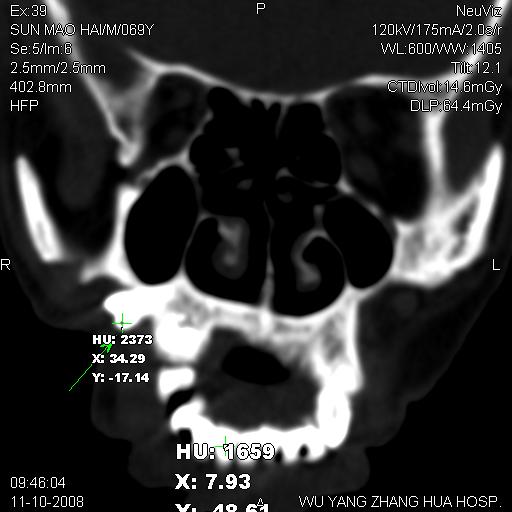

标题: CT16568:右面部瘘管半年余,无其它不适.

考虑右上颌异位齿(或斜向阻生齿)并根尖脓肿。

1.右上颌异位齿

2.右上颌化脓性骨髓炎

3.右下鼻甲肥大